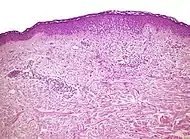

Interface dermatitis

These are sorted into either:[2]

- Interface dermatitis with vacuolar change

- Interface dermatitis with lichenoid inflammation

Interface dermatitis with vacuolar change

| Generally/Not otherwise specified | Typical findings, called "vacuolar interface dermatitis":[6]

An interface dermatitis with vacuolar alteration, not otherwise specified, may be caused by viral exanthems, phototoxic dermatitis, acute radiation dermatitis, erythema dyschromicum perstans, lupus erythematosus and dermatomyositis.[2]